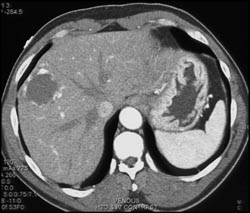

Cavernous Transformation of the Portal Vein (CTPV)